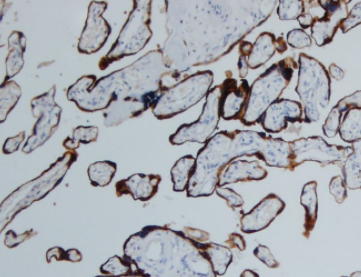

人绒毛膜促性腺激素(hCG)抗体是一种特异性识别妊娠相关肽激素的检测工具,主要用于标记滋养层来源的细胞和肿瘤。hCG由胚胎着床后产生(后期由合体滋养层细胞分泌),其核心功能是通过维持黄体孕酮分泌来保障妊娠,同时参与调节妊娠免疫耐受过程。该抗体在病理诊断中具有重要价值:①能特异性检测绒毛膜癌等滋养层肿瘤;②在非滋养层肿瘤中,肺大细胞癌(90%阳性)和肺腺癌(60%阳性)呈现较高表达率,肺鳞癌亦有20%阳性率。值得注意的是,hCG在非滋养层肿瘤中的表达可能提示侵袭性生物学行为,因其参与调控肿瘤宿主免疫反应,这使得该抗体不仅成为妊娠检测和滋养层疾病诊断的金标准,也为评估某些恶性肿瘤的预后提供了潜在分子标志。

阳性部位:

细胞质